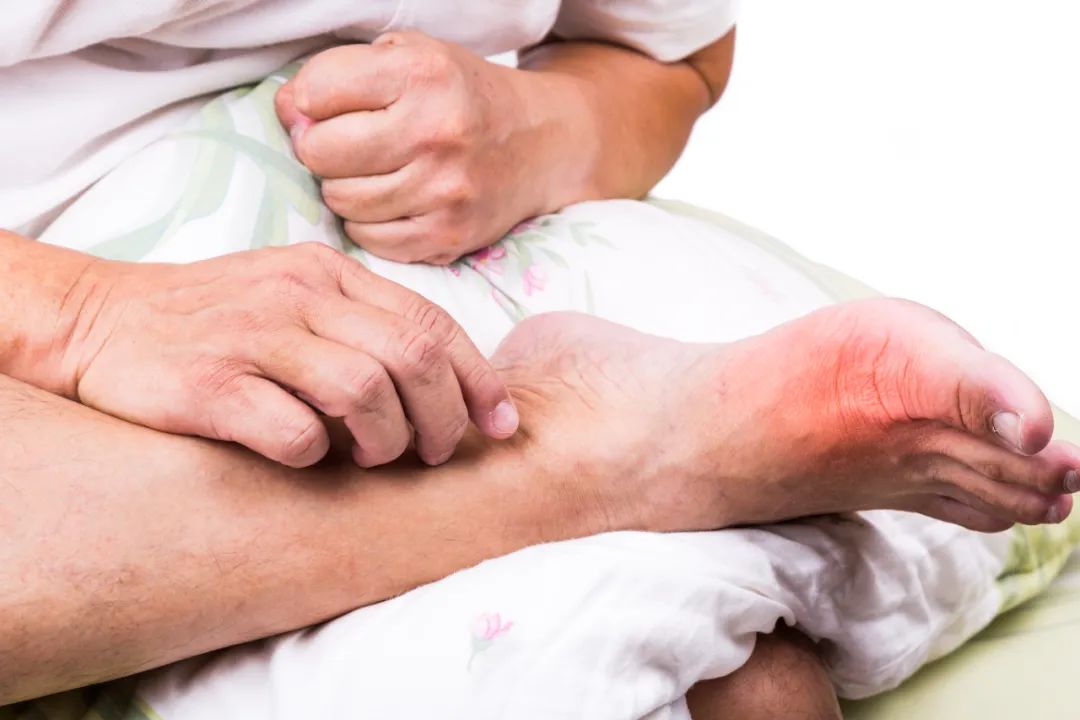

痛风主要由人体内过高的尿酸引起,由于尿酸过高而血液又无法完全溶解,就会导致一部分尿酸沉积在身体的各个部位,尤其是四肢,形成尿酸盐结晶(俗称痛风石),进而产生疼痛感。

试想一下,有沙子掺进鞋里,走起路来都会难受。如同沙子一样的痛风石在关节内产生摩擦,能不疼吗?

痛风石通常出现在哪儿?一般在耳廓、关节周围、肌腱、软组织等周围皮下可见。